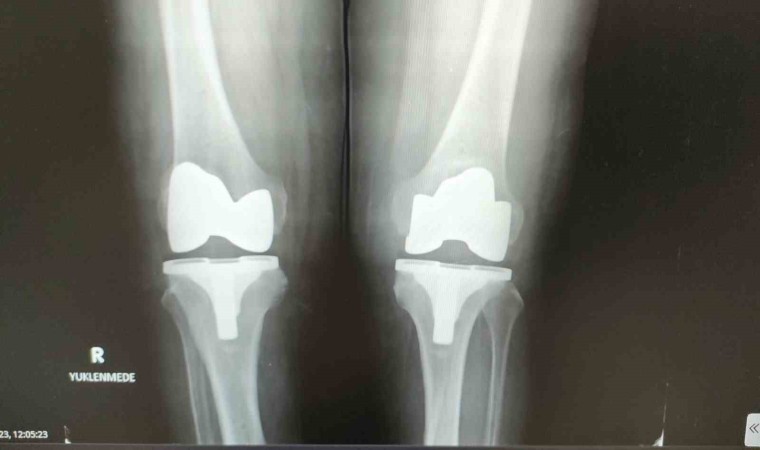

Protezin ağrılı bir işlemden önce uygulandığını dile getiren Baloğlu, “Kireçlenme dediğimiz durum olunca, iki kemik birbirine sürtüyor, hasta ayağa kalktığında, hatta sonraki dönemlerde istirahatte bile ağrıdan dolayı duramıyor. Bırakın yürümeyi normal istirahat ağrısı, gece ağrısı oluyor. Dolayısıyla bu hastalar bize, ‘Beni ameliyat edin’ diye geliyor. Çoğu hasta grubumuz böyle. Robotik protezler diğer protezlere göre şöyle bir farklılığı var; biz bu protezi hastaya özel ürettiriyoruz. Ameliyat öncesinde tomografi ve filmler sisteme yükleniyor. Sistem sayesinde protezler hastaya özel üretildiği için, kişiye özel olarak gelmiş oluyor. Bu protezi robotik yardımlı olarak ameliyatta hastaya uyguluyoruz. Bu işlem kabaca yarım saat 45 dakika sürüyor” dedi.

Hastanın bir iki gün hastanede kaldıktan sonra yürür şekilde taburcu olduğunun altını çizen Baloğlu, “Bu ameliyatta daha az kesiden işlem yapıldığı hem de hastaya özel protez kullanıldığı için hata payımız neredeyse sıfır. Bu nedenle hasta da bir ay sonra geçirdiği bu işlemi neredeyse unutmuş olur.

Yürüme sıkıntısı çeken hasta rahatlıkla yürüyerek çıkıyor. Çünkü ağrı olmadığı zaman hasta zaten yürümek istiyor ve bunu biz de talep ediyoruz. Dolayısıyla bundan sonrasında, ‘aman yürüme üzerine basma’ demiyoruz. Tam yükle mobilize olur şekilde hasta gidebilir buradan. Özellikle namaz kılma noktasında zorlanan yaşlılarımızdan çok soru geliyor. Robotik protezlerin dizaynında mobil dediğimiz hareketli protezlerde namaz kılma anlamında bir engel durum yok. Biz bunu gerekli rehabilitasyon yapıldıktan sonra hasta sandalye ya da başka bir şey kullanmadan namazını kılabilir” ifadelerine yer verdi.